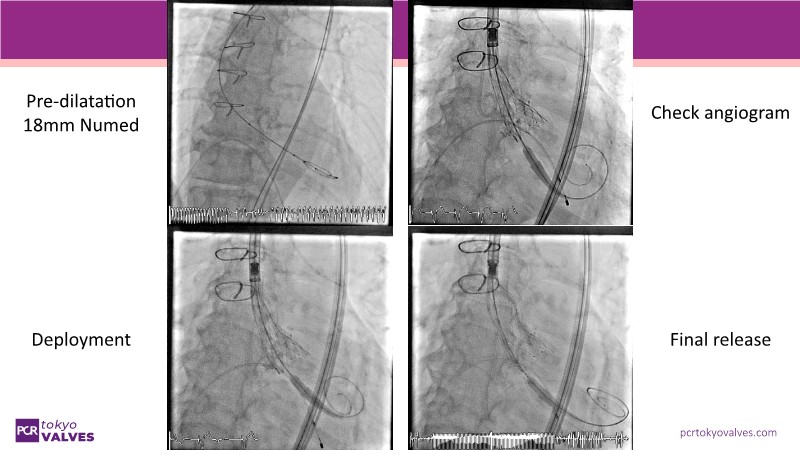

Watch this expert-led session on the latest Evolut TAVI advancements, device selection for small annulus cases, and strategies for complex anatomies. Learn about redo-TAVI feasibility and key 1-year data from the SMART trial.

• To master implantation techniques and discern the latest technological evolutions for treating patients with complex anatomies